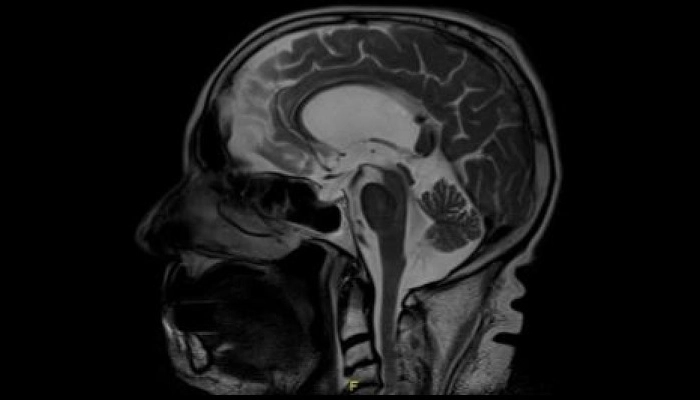

Hình ảnh MRI não với dấu hiệu “chim cánh cụt” (hummingbird sign) trong liệt trên nhân tiến triển

Chẩn đoán chủ yếu dựa vào lâm sàng và hình ảnh học như MRI để loại trừ bệnh khác.